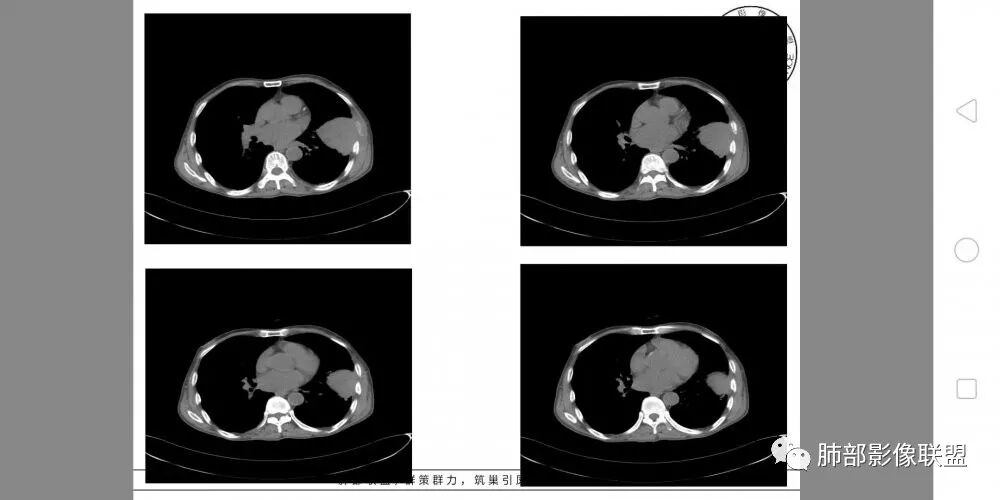

胸部CT所见左肺上叶尖后段胸膜下较大山丘形肿块,边界清楚,宽基底与胸膜相贴,边缘与胸膜呈直角及锐角相交。邻近上叶尖后段支气管受压推挤,叶裂局部膨隆,病灶周围见少许磨玻璃密度影,边界不清。纵膈窗显示,肿块密度均匀,增强扫描呈不均匀轻度强化,邻近肋骨骨质破坏,病变沿肋间隙向外侵犯,局部胸膜增厚。纵膈内见多发小淋巴结,未见胸腔积液征象。综合考虑恶性占位,肉瘤样癌可能性大。腰椎及髋部考虑骨转移。

胸壁来源符合吗?

不符合,因为病灶的主体在肺内,而且胸膜在病灶的外侧为主

与胸膜非钝角相交

如果是外面长进来的,胸膜掀起的角度一般更大,呈钝角

我们换个角度讲,如果是胸壁肋骨来源,病灶外朝内生长,并且朝内生长这么大,按理说应该是内侧侵袭性强,外侧侵袭弱。但是看这个病灶,外侧边界反而不清,内侧边界清,整个形态不太符合肋骨来源,而且胸膜局部增厚也不太符合胸壁来源。我认为肋骨来源应该以肋骨为中心,偏侧可以,但不会这么明显。而且血供也不一致,应该是肋间或胸壁动脉明显。

肋骨内侧面破坏为主,朝外有轻微的推移迹象。我觉得胸壁来源的放后面,特别是支气管的堵塞,这是肺外病变很少见的,SFT也有,罕见。

综合考虑恶性肿瘤,外朝内发展,倾向于肺内来源。

鳞癌因为侵袭性力较强,容易直接侵犯胸膜、胸壁,而周围型肺癌侵犯胸壁的90%癌肿是鳞癌,这也是鳞癌的一个特征性表现。邻近胸壁的脂肪层消失,胸壁肿块形成或有肋骨皮髓质边界不清的侵蚀破坏(而非边缘硬化或崩解)是瘤体向周围直接侵犯的可靠征象。

肉瘤样癌也好发于中老年人,与吸烟关系密切。肿块体积往往较大,也是好发于胸膜下伴胸壁侵犯,也容易发生坏死,与周围型鳞癌的主要鉴别点在于支气管的关系和病灶内强化的情况。肉瘤样癌以环状强化为主,病灶周边多以癌组织为主,血供丰富,病灶中心区则以肉瘤成分为主,血供较差,易出现粘液样变性、坏死、出血,坏死边界清楚。